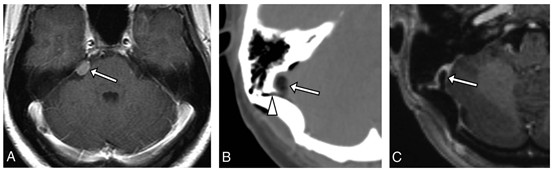

在颅骨手术止血方面,骨蜡也是常用的止血材料。然而,有文献报道骨蜡的使用可能会迁移至重要血管结构[6]。该研究回顾性分析了212例接受后颅窝手术(如乳突切除术、乙状窦后开颅术)并术后行CT及增强MRI检查的患者,结果发现有6例(2.8%)患者存在乙状窦骨蜡迁移情况(图3)。

图3 A. 轴位增强T1WI显示岩骨嵴处小脑膜瘤(箭头)。B. 术后轴位CT(无增强)显示乙状窦内低密度团块(约162 HU,箭头),邻近开颅手术区域,并延伸至乳突导静脉管(箭头头)。C. 术后轴位增强T1WI显示乙状窦内低信号填充缺损(箭头),符合骨蜡迁移特征,即使未使用脂肪抑制技术,信号仍然较低。